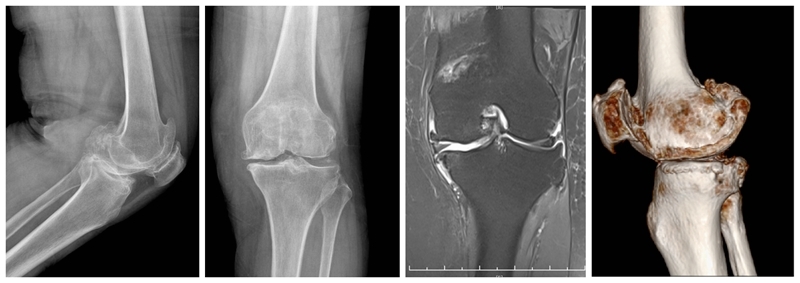

内侧单髁置换术(非骨水泥型)

术前

术后检查

膝关节单髁置换术后的翻修率的一个主要原因是无菌性假体松动。临床上常常用术后X线平片上是否出现透亮带来判定假体是否松动。事实上部分骨水泥型单髁假体,术后x线片常常可见生理性透亮带,容易误诊为假体松动,从而导致不必要的术后翻修,生物型单髁置换假体的推广减少了单髁翻修率,延长了假体的使用寿命。

现阶段生物型单髁假体也逐步被越来越多医生与患者选择。对于生物型假体,需要注意以下几点:(1)垂直截骨开槽避免用常规骨水泥型假体工具,以免开槽过宽导致假体置入松动。(2)开槽过程中需要特别谨慎小心,敲击力度适宜,以防胫骨劈裂骨折。(3)年龄大,骨质疏松明显以及股骨髁坏死病例用生物型假体应更加慎重。

高龄患者内侧单髁置换术

对于80岁以上的高龄膝关节骨关节炎患者,准确手术评估、恰当围术期处理、选择微创UKA,不仅有效,而且安全可行。与TKA相比,高龄患者采用UKA治疗不仅有效,还具有并发症少、输血率低、住院时间短、恢复快等特点。但是,高龄膝关节骨关节炎患者通常合并较多内科疾病,围术期科学管理尤为重要。应注意以下几点:术前高血压患者血压应控制在160/90 mm Hg以内;糖尿病患者血糖应控制在10.0 mmol/L以内,尿糖(+++);冠状动脉粥样性硬化病患者适当给予扩张冠脉及营养心肌治疗,超声心动图示左心室射血分数超过 50%以上;心律失常患者完善24 h动态心律检测,必要时请心内科协助诊治;慢性肺部疾病患者肺功能最大通气量超过 60%以上。另外,术前需关注贫血及低蛋白血症情况,必要时给予输血或补充白蛋白治疗。熟练操作、严格微创、减少手术时间及术中出血是手术成功关键。

合并ACLD的单髁置换术

ACL损伤是否适合单髁置换,争议较大。需要鉴别原发韧带损伤继发OA还是原发OA继发ACL损伤。前者一般年龄轻,运动量大,适合一期或二期UKA联合ACL重建,后者一般年龄偏大,运动量少,需要术前详细评估膝关节稳定性。UKA仍是治疗内外不稳定的一种选择,而前后不稳定应探索其他治疗方案。髁间窝骨赘作为膝关节二级静态稳定结构。手术中引起撞击或磨损的骨赘要完全去除,其它骨赘建议保留。必须保留所有残留的ACL。适度减少胫骨后倾,一般应小于5°。

非骨对骨内侧OA单髁置换术(PTCL

一般认为应力位片非骨对骨接触,可以借助MRI或术中关节镜探查明确原因,对于残留软骨<25%可考虑单髁置换。总体而言,非骨对骨单髁置换手术疗效低于骨对骨单髁置换术。

严重内翻畸形单髁置换术

严重内翻畸形需要明确畸形原因,对于骨缺损明显,膝关节僵直畸形,合并内侧副韧带挛缩,畸形>20°病例不适合。对于在外翻应力位可以矫正的关节内的内翻畸形,只要前交叉韧带完整,仍然可以谨慎选择UKA。术前仔细评估骨质磨损深度,骨缺损,内侧副韧带张力及膝关节稳定性。备好全膝关节假体。术中注意避免截骨过深,导致间隙过大,常规厚度假体不能满足需要。骨质缺损较多一般推荐使用固定垫片假体。注意保护内侧副韧带,避免截骨损伤。

活动度小于90度内侧单髁置换术(ROM < 90°)

经典的单髁手术一般膝关节需要至少屈曲至110°,术前低于90°一般不适合单髁置换。需要明确术前屈曲受限的具体原因,对于屈曲受限因后方骨赘增生阻挡的病例术中可以改善屈曲度。部分病例可能术后仍然不能恢复正常的屈曲度,功能一般不受影响。